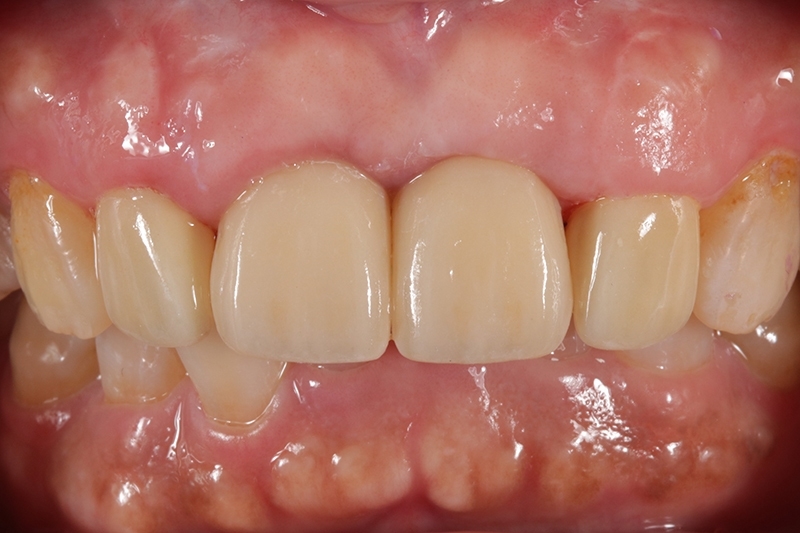

門牙植牙全瓷冠+側門牙全瓷冠完成照

術前術後對照圖

術後